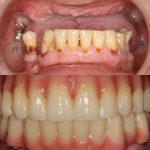

Casos de antes y después de los implantes dentales

Descubra los testimonios de nuestros pacientes tras realizarse su tratamiento de implantes dentales

Devolvemos la sonrisa y la calidad de vida a nuestros pacientes

En IDIM contamos con más de 40 años de experiencia y dedicación a la implantología dental. Con especialización, técnicas innovadoras y una amplia experiencia, abordamos los casos más complejos de implantología dental.Nuestra misión es ofrecer el mejor servicio de implantes dentales en Valencia. Buscamos la integración natural de las prótesis sobre implantes dentales, logrando sonrisas saludables y radiantes que permiten a nuestros pacientes vivir plenamente.